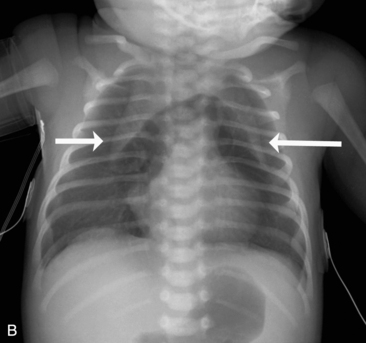

Children older than 6   years have mediastinal structures comparable to those of adults. The thymus shadow, seen in the upper third of the chest at the mediastinum, has bilateral lobes. The thymic silhouette blends almost imperceptibly with the cardiac silhouette, because it occupies contiguous space, giving the appearance of a widened mediastinum. It can produce a triangular shadow, resembling the sail of a boat (called the sail sign). The thymus is most often visualized on the chest radiograph from birth to 2   years of age, but may persist up to 5   years of age6,16,17,25 (Fig. 10-9).

image image

Fig. 10-9 Normal thymus. A, This supine anteroposterior film demonstrates the right lobe of the thymus projecting over the right upper lung field, creating the appearance of a widened mediastinum. The triangular shape (arrows) is the classic appearance of the sail sign (the right lobe of the thymus forms a triangular shape characteristic of the sail of a boat). B, This infant has a pneumomediastinum that has elevated the right and left lobes of the thymus (arrows) off the heart.

(B, Courtesy Sharon Stein, Nashville, TN.)